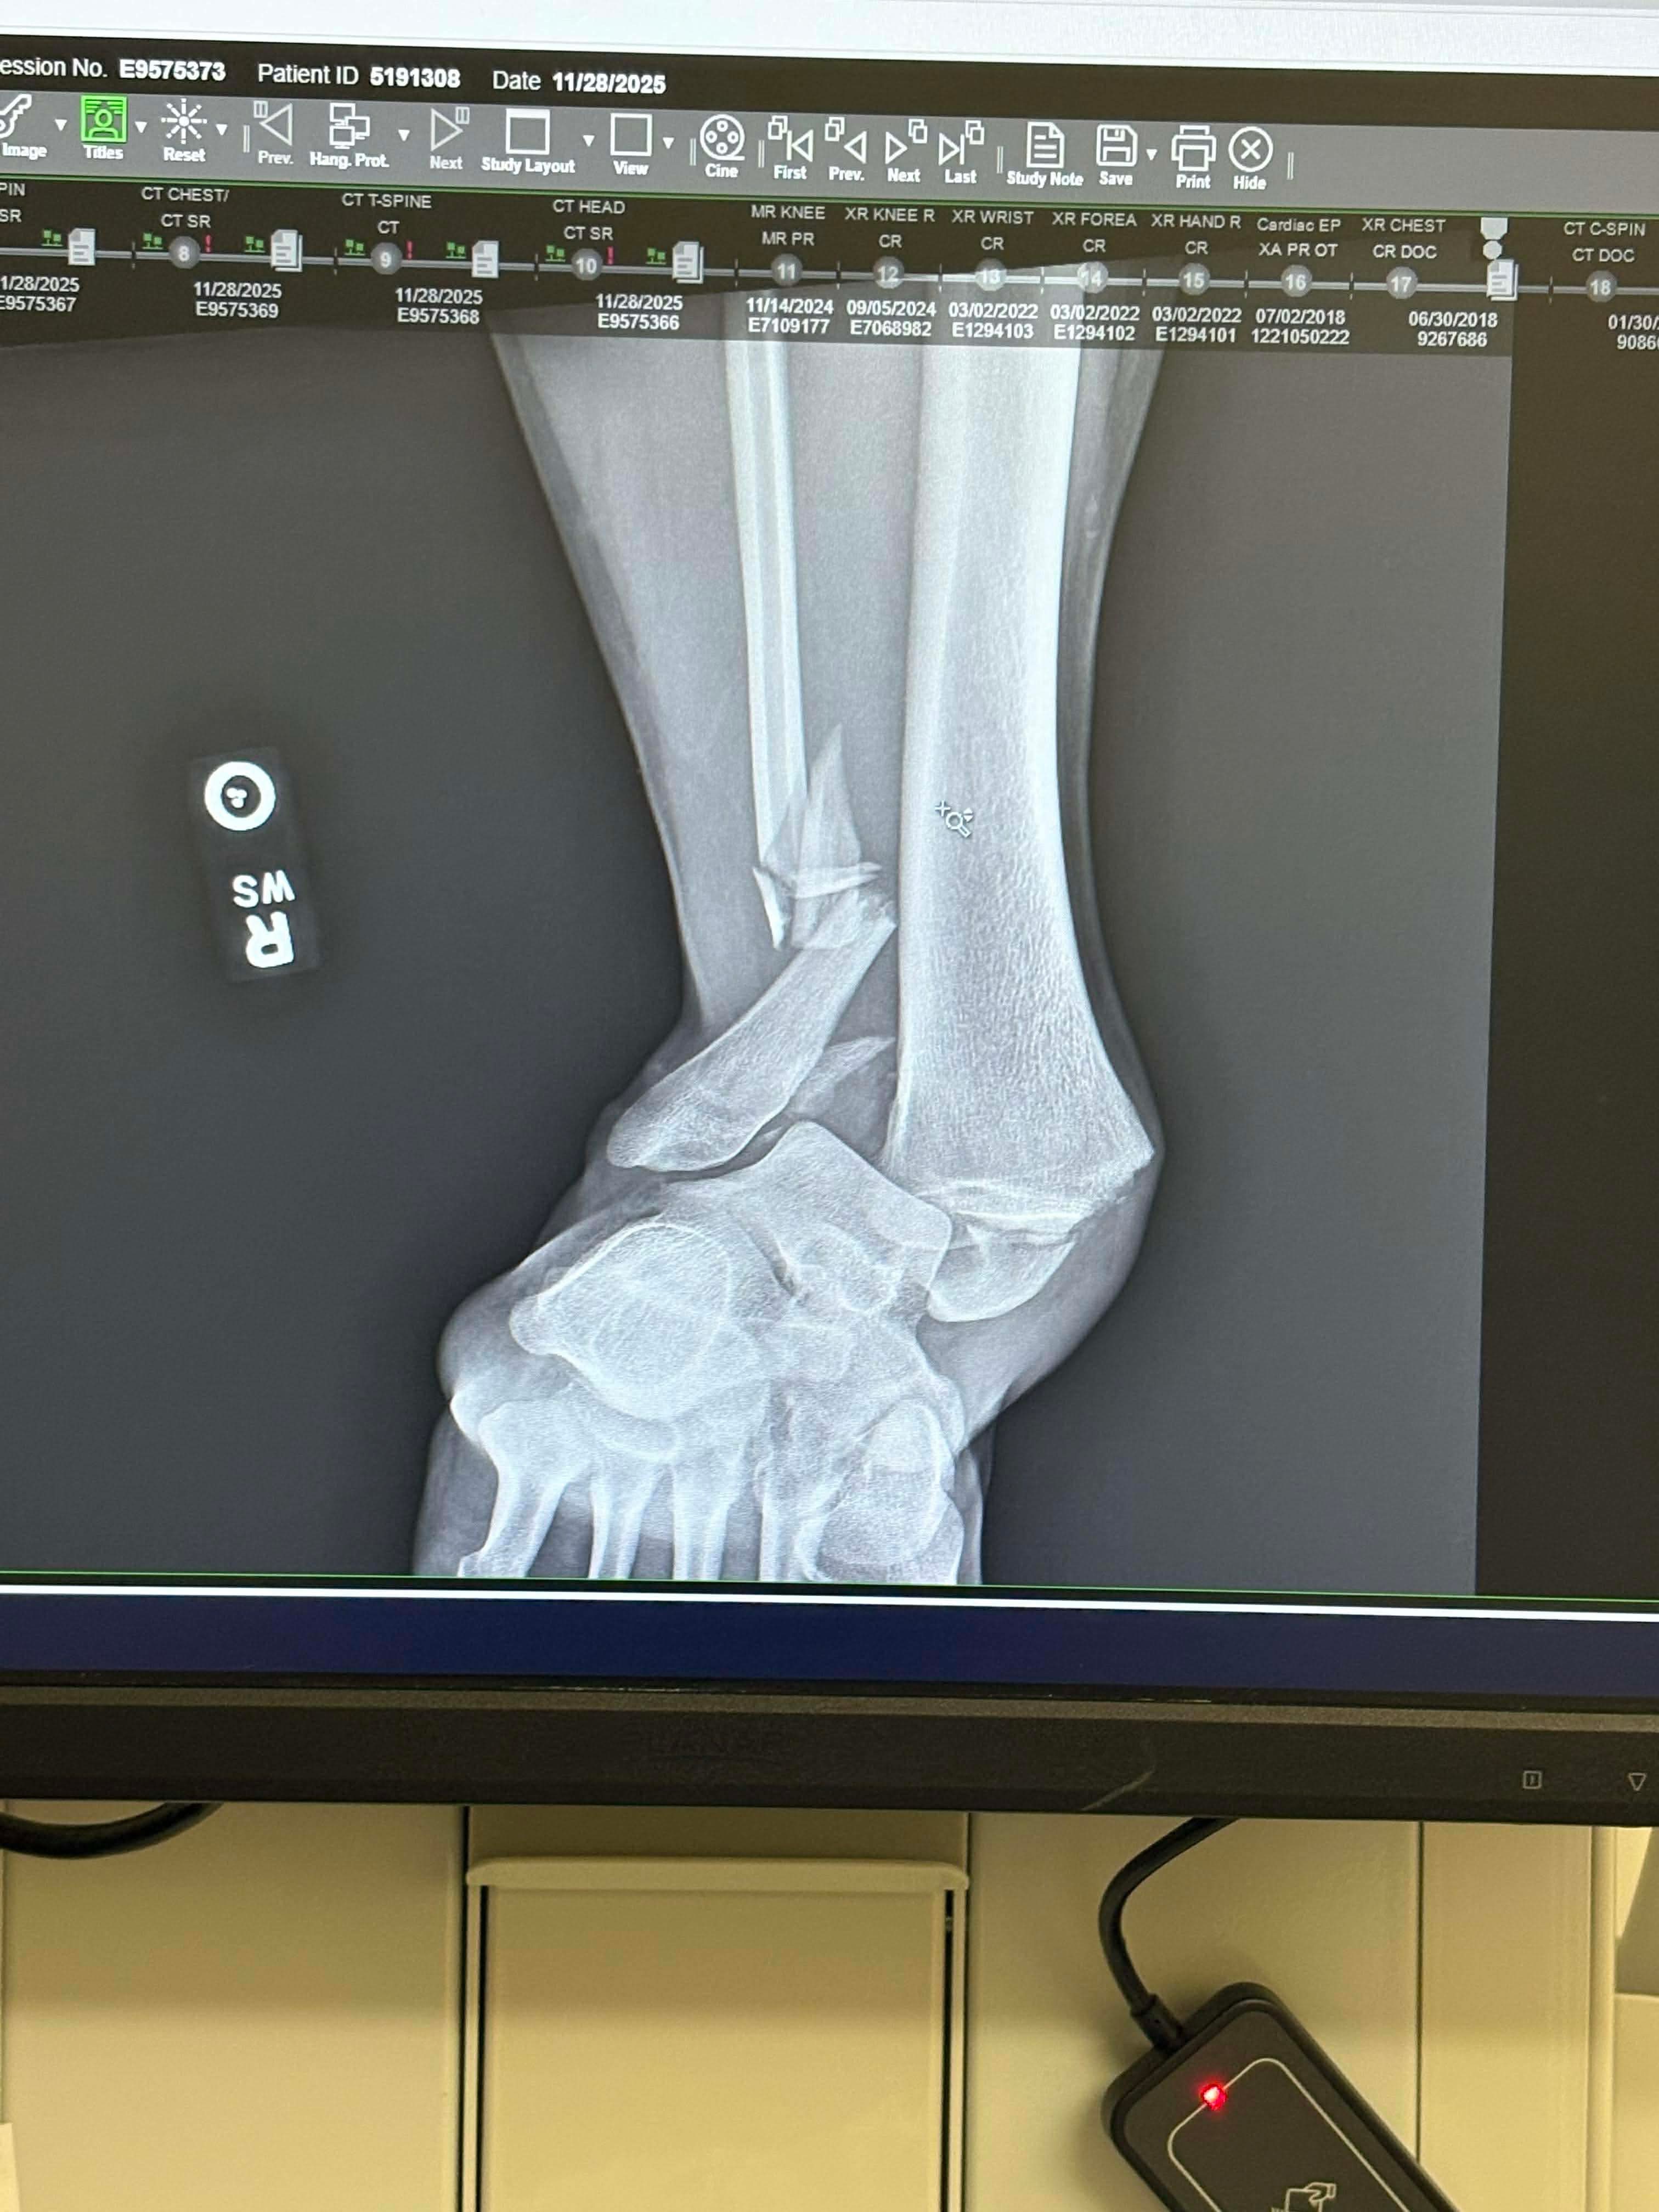

Ended up losing traction while driving in the snow and hit a tree. I broke my tibia, fibula, and ankle bone, gashed my eyebrow open (needed six stitches), broke some ribs, and bruised both lungs.